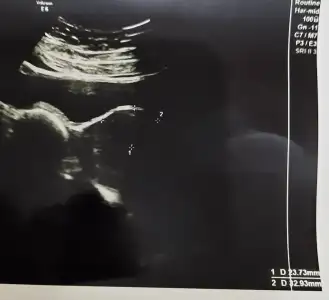

bizim yapabileceğimiz düzenli takip etmek ilaclarini düzenlemek erken doğum riski görürsek ciğer geliştirici vurmak dedi. kuvoz ihtimali hep var. gerisi Allah Kerim ne yapalım. bundan sonra hep 2 haftada bir bakicakmis. erken dogum kaderimiz gibi biseymis ikiz gebelerin yüzde 60i erken dogum yapiyormus zaten. kendi hastalarindan da bunlarin yariis kuvoze giriyormus yarisi girmiyormusBugünkü randevuda mi dedi böyle? İyi rahatlatmiş doktor içini valla.

Teşekkürler 19+3teyim

bugun söyledi evet. idrar tahlili vermistim zaten temiz cikmisti. vajinal muayene etti orda da bir enfeksiyon bulgusu gormedi